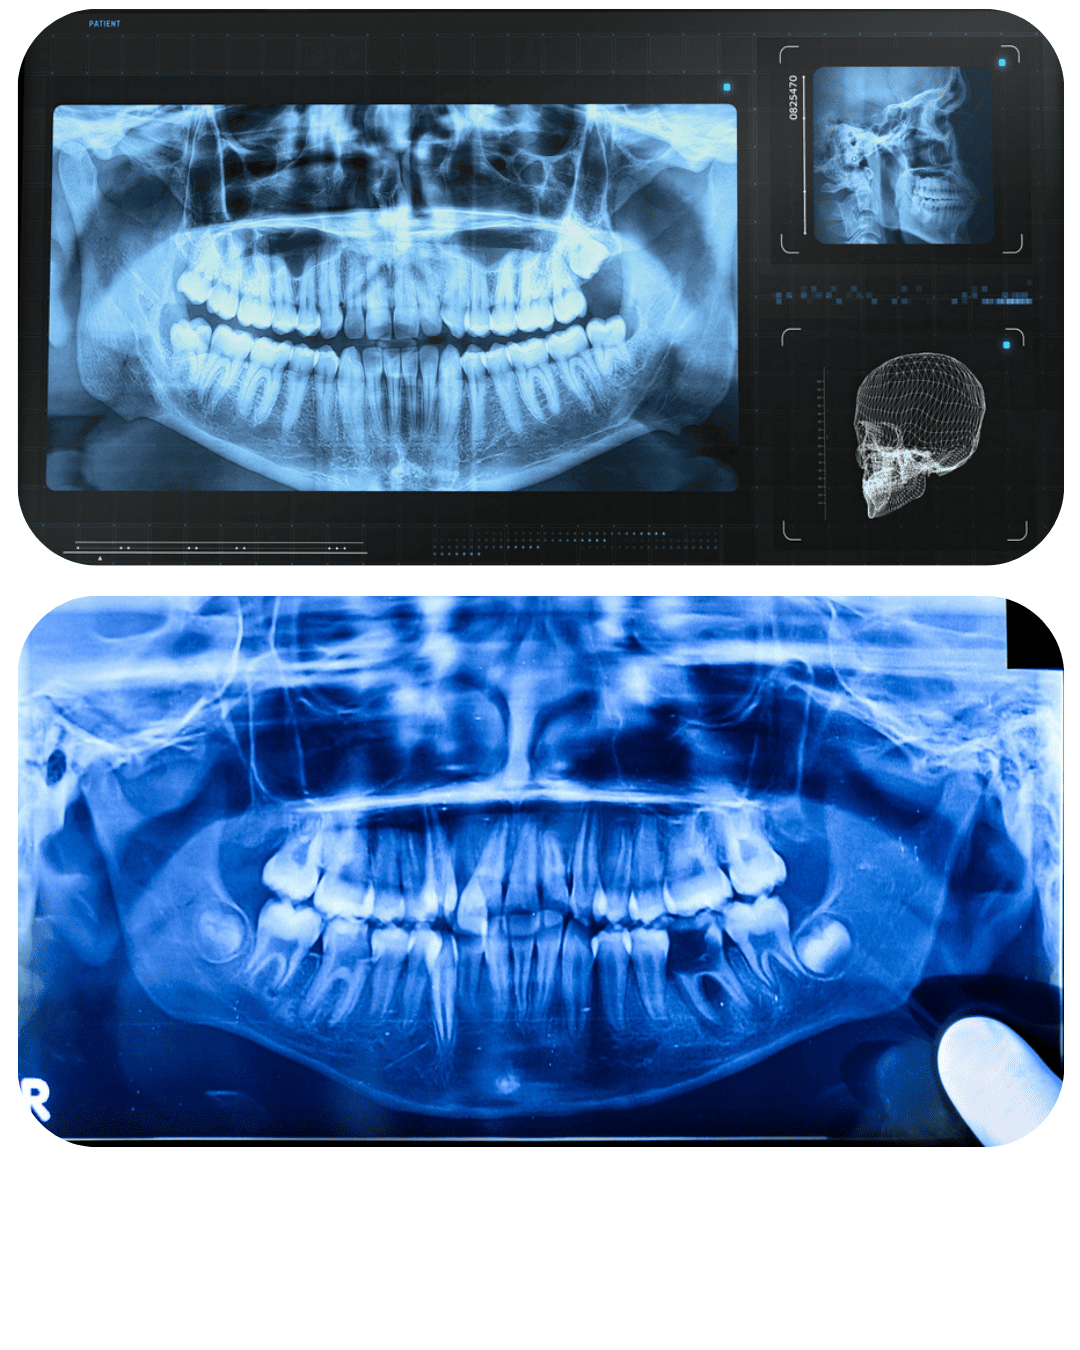

CBCT

(3D DIJAGNOSTIKA)

CBCT pruža 3D prikaz zuba, kosti i mekih tkiva uz visoku rezoluciju. Nezamjenjiv je pri planiranju implantoloških, oralno-kirurških, endodontskih i složenih dijagnostičkih zahvata, jer omogućuje maksimalnu preciznost i predvidljivost terapije.